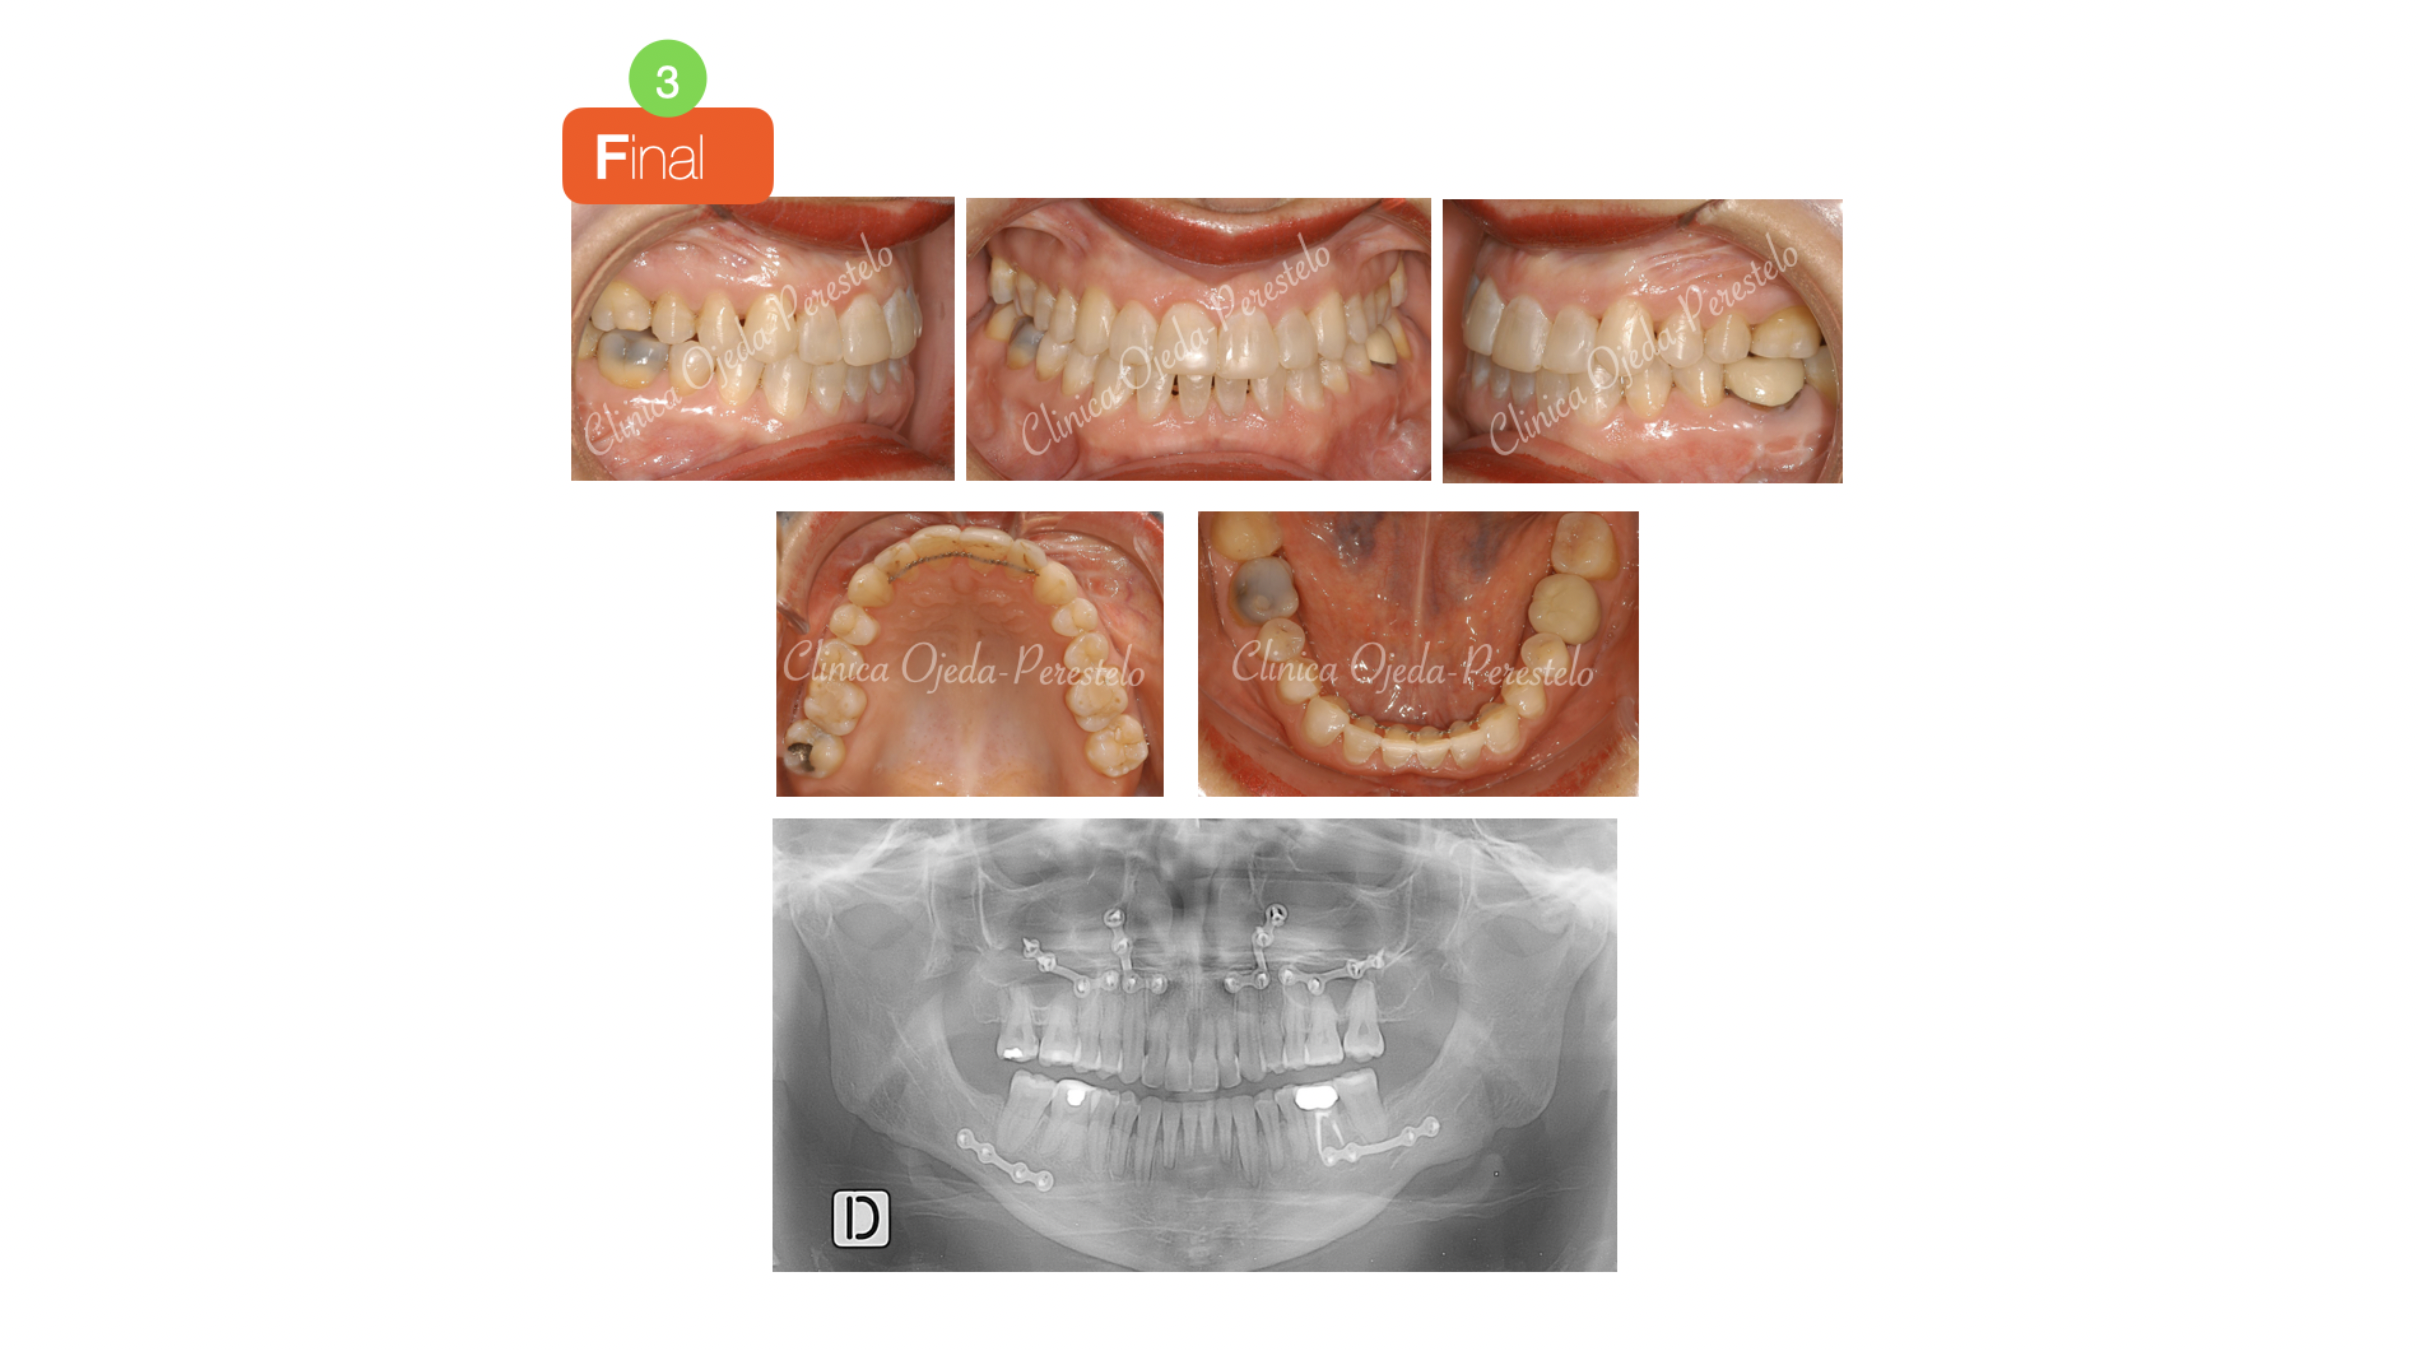

La intervención es realizada por el equipo del Dr Hdez-Alfaro fue planificada con Lefort y Avance del Maxilar conjuntamente con Osteotomia Sagital de Rama para centrado y retrusión Mandibular. Las dolencias articulares y musculares han desaparecido en su totalidad.